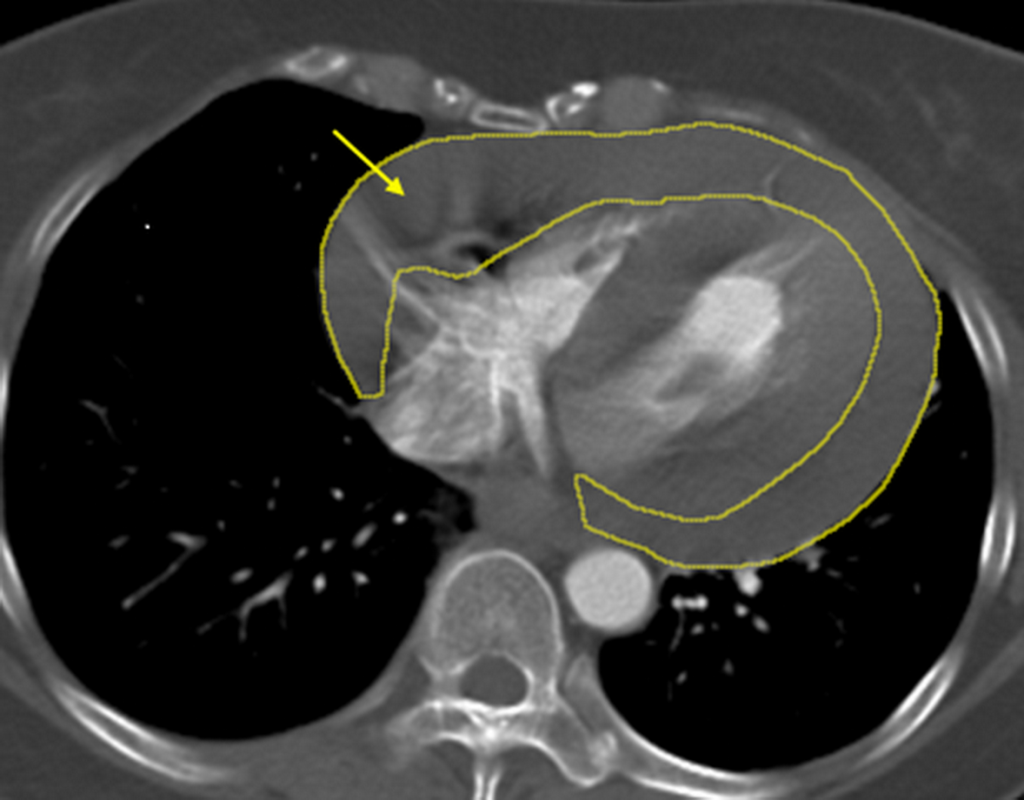

46歲陳小姐日前騎機車返家途中,突感頭暈、意識不穩而失控摔倒,緊急送抵土城長庚醫院時已陷入休克狀態;緊急診查發現陳女心臟外層已迅速累積大量心包積血,高度懷疑合併外傷引發的升主動脈剝離,經緊急啟動跨科整合搶救機制,在關鍵72小時內接力完成「劍突下心包開窗術」、「升主動脈置換術」、「胸骨固定」等重大手術,成功將陳女從生死關頭拉回。

針對陳女這次暈倒休克,經影像檢查確認為大量心包積血,醫療團隊第一時間成立跨科搶救小組,由心臟外科緊急執行「劍突下心包開窗術」,迅速解除心臟壓迫、穩定循環;隨後無縫銜接由血管外科進行高難度的「升主動脈置換術」,以人工血管重建破裂的主動脈。在術後並陸續完成止血、調整及胸骨固定等關鍵處置,終於順利挽回陳女一命。